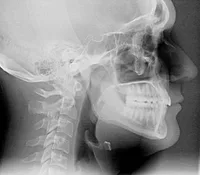

QUIZ Radiografi Ekstra Oral

Penamaan teknik radiografi ekstraoral ditentukan berdasarkan posisi kepala pasien

Garis referensi untuk pengambilan radiograf ekstra oral disebut orbitomeatal line, yang posisinya sejajar dengan garis Frankfurt Horizontal Plane.

Perbedaan mendasar antara teknik radiografi ekstra oral dan intra oral adalah pada posisi peletakan film/ image receptor terhadap pasien

Proyeksi Waters diindikasikan untuk memeriksa area sinus maxillaris dan sinus paranasal lainnya.

Proyeksi postero-anterior dengan proyeksi reverse towne mempunyai kemiripan posisi pasien dan arah konus sinar-X, perbedaannya adalah pada proyeksi postero-anterior pasien diminta untuk membuka mulut.